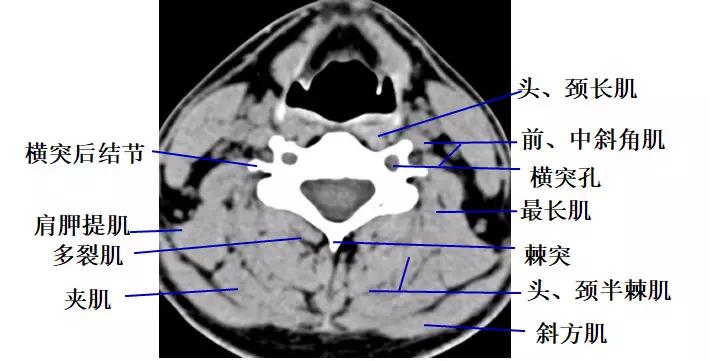

3.经颈椎椎弓根的横断层面(CT)